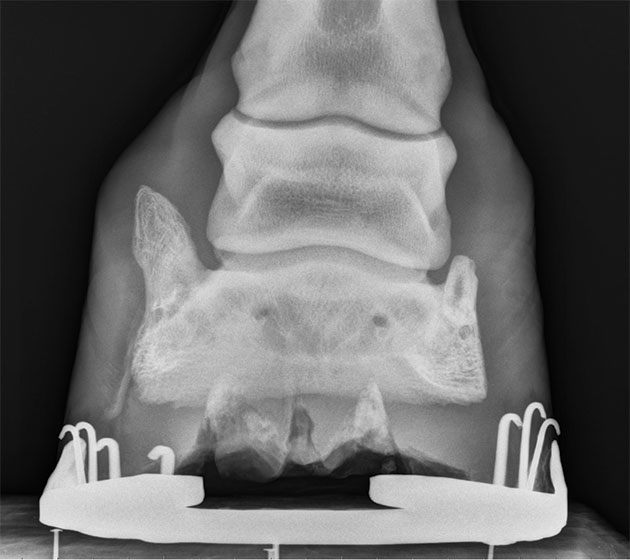

While most horses don’t exhibit lameness with sidebone, it is easily spotted and looks alarming on an X-ray. “In general, for most horses, it’s not a source of lameness,” says Dr. Durham. “It gets blamed a lot of times because it’s there and easy to see radiographically, but often it’s an incidental finding.” The boney protrusions can also be felt by palpating on the outside of the pastern, and severe cases may even be sensitive to touch. Horse owners are usually in shock when seeing them so plainly on the X-ray because their horses are generally showing no signs of being sore. “Even if the horse is limping, and we know that sidebone is present radiographically,” Dr. Durham says, “I’m usually looking for something else because it’s uncommon for that to be the cause.” One of those potential problems is an injury to the collateral ligament of the coffin joint that stabilizes both sides. This injury has been correlated with the presence of sidebone. For this reason, medial- lateral balance of the hoof is a critical issue in affected horses.

“In general, for most horses, it’s not a source of lameness,” says Dr. Matt Durham. “It gets blamed a lot of times because it’s there and easy to see radiographically, but often it’s an incidental finding.”